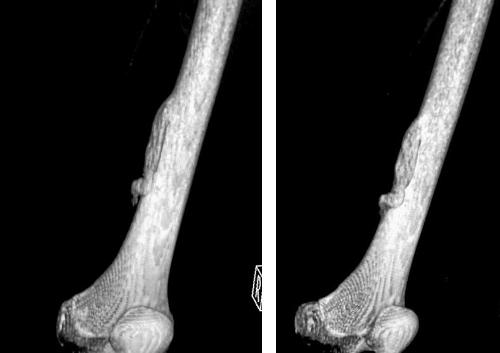

При диагностике следует дифференцировать остеому от солидной одонтомы, реактивных разрастаний костных тканей, оссифицированной фиброзной дисплазии, которые могут возникать в следствие инфекционных поражений или тяжелых травм. На начальных стадиях заболевания назначаются дополнительные методы исследований — рентгенография, информативная компьютерная томография. В зависимости от места расположения лечением данной доброкачественной опухоли занимаются челюстно-лицевые хирурги, нейрохирурги, травматологи.

Диагностика остеоид-остеомы включает рентгенографию, которая может показать характерные изменения в костной ткани, такие как небольшая луковичная область с остеосклерозом. В некоторых случаях может потребоваться компьютерная томография (КТ) для более точного определения размера и локализации опухоли. Также может быть назначено магнитно-резонансное исследование (МРТ) для оценки состояния мягких тканей вокруг опухоли.